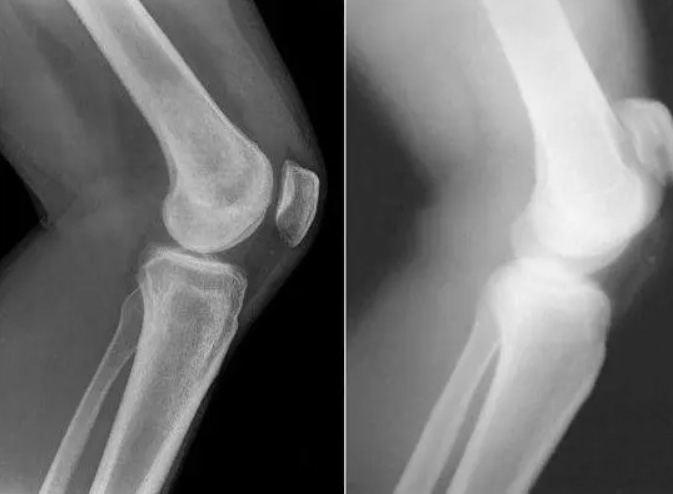

Restauration de l'articulation du coude. Patiente, 31 ans. Durée du traitement par la Marukaya Сream : 12 jours. Son articulation est entièrement restaurée :